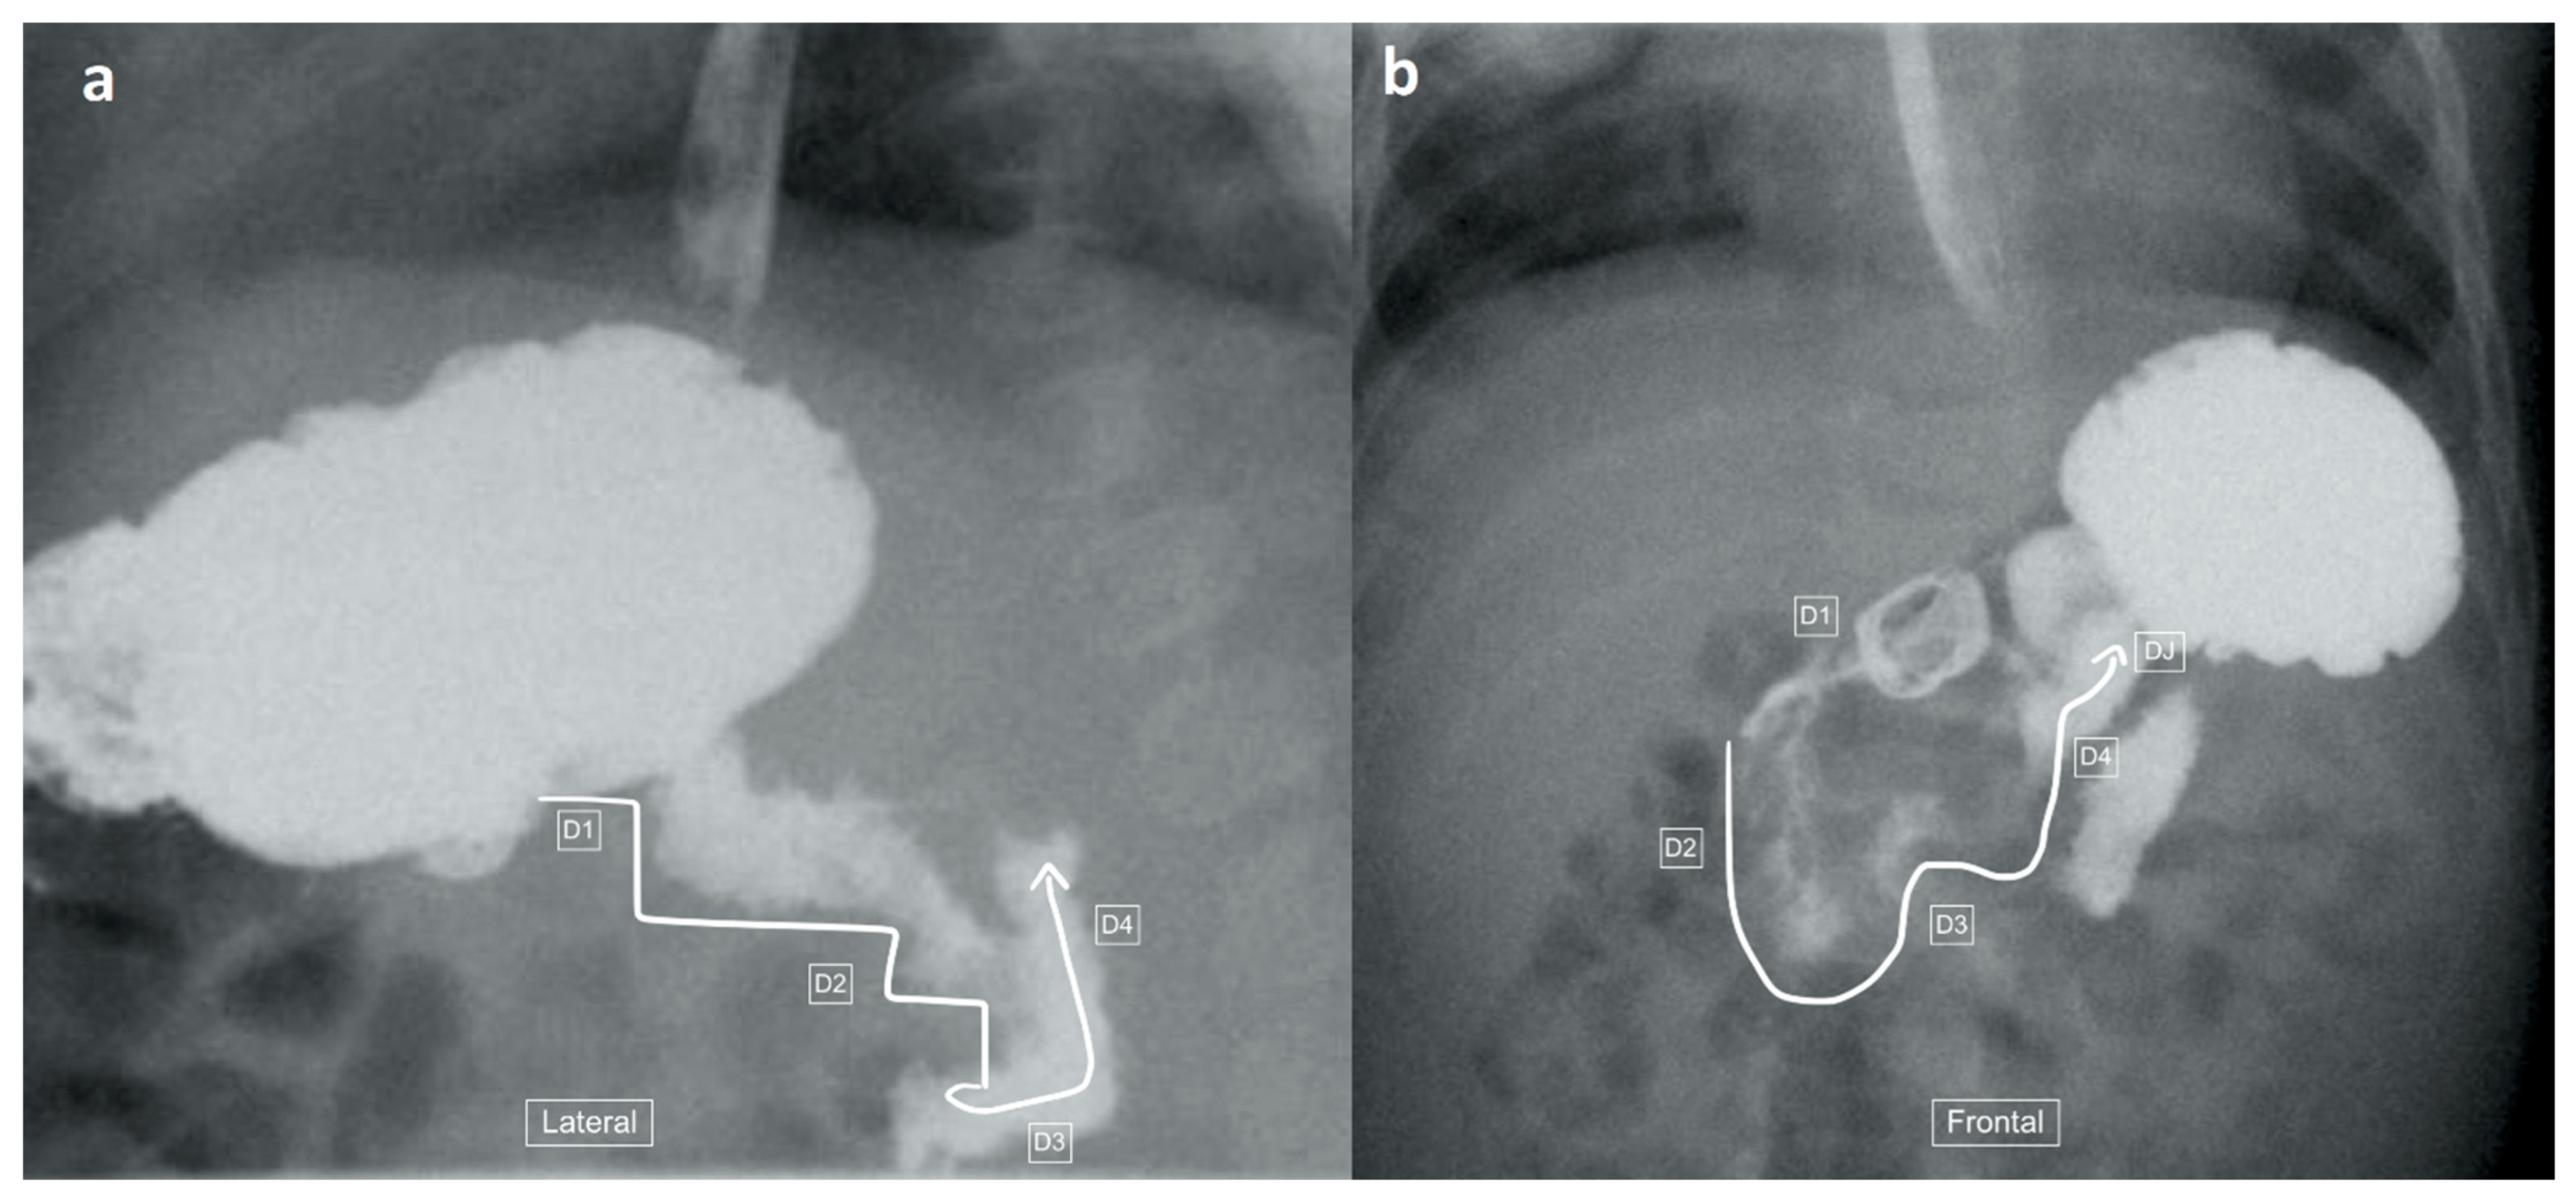

Figure 8.

Upper-gastrointestinal tract series in a 159-day-old girl with a false–negative lateral view and a diagnosis of malrotation on the frontal view. (a) Lateral view demonstrates what appears to be a normal course of the duodenum (winding arrow) into its posterior retroperitoneal position, with a presumed normal position of the duodenojejunal flexure, before the jejunum takes and anterior course. (b) Frontal view, considered the standard for this study, demonstrates the duodenal loop (from D1 through D2, D3 and D4 denoted by the winding arrow) and a caudal (low) position of the duodeno-jejunal flexure (DJ) in comparison to D1 (the positional differences denoted by the dashed lines), consistent with malrotation.